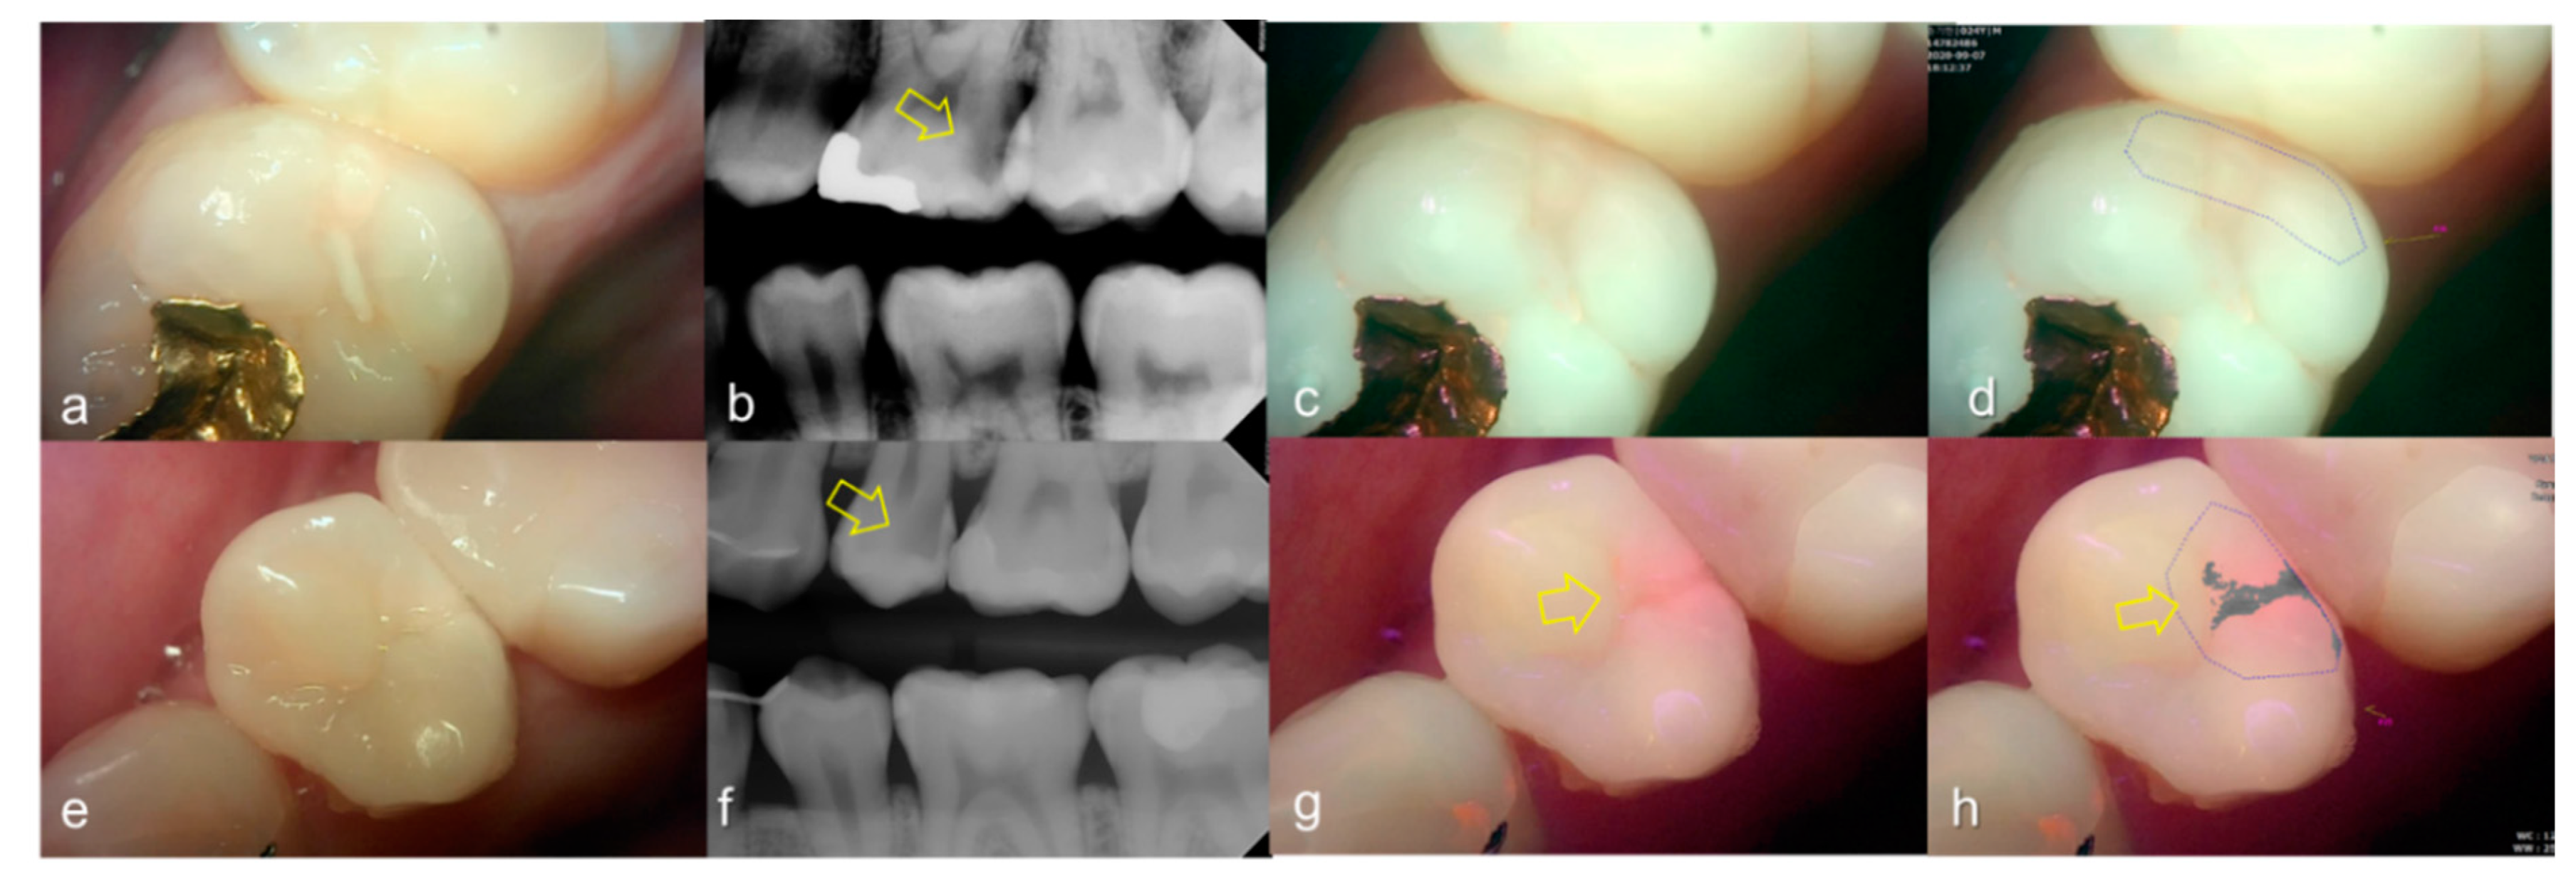

Representative images of QLF and bitewing radiograph of occlusal dental caries are shown in Figure 4 and Figure 5.

Figure 4.

Occlusal dental caries: (a–d) QLF caries score 1 (fluorescence loss and red fluorescence present as a line or spot in pits and/or fissures) and radiographic caries score 0 (no radiolucency visible) on #36; (e–h) QLF caries score 2 (fluorescence loss and red fluorescence glow extending around pits and fissures) and radiographic caries score 0 (no radiolucency visible) on #36; (i–l) QLF caries score 3 (red fluorescence glow extending around pits and fissures and a dark shadow from dentin present) and radiographic caries score 0 (no radiolucency visible) on #37; (a,e,i): white-light image of QLF; (b,f,j): fluorescence image of QLF; (c,g,k): bitewing radiograph; (d,h,l): analyzed QLF image using QA2 software.